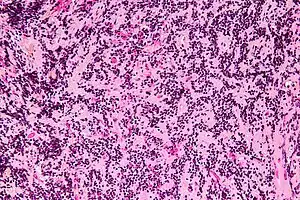

| Micrograph of a pineocytoma. HPS stain. | |

Pineocytoma, is a benign, slowly growing tumor of the pineal gland. Unlike the similar condition pineal gland cyst, it is uncommon.

Pineocytomas are diagnosed from tissue, i.e. a brain biopsy.They consist of:

- cytologically benign cells (with nuclei of uniform size, regular nuclear membranes, and light chromatin) and,

- have the characteristic pineocytomatous/neurocytic rosettes, which is an irregular circular/flower-like arrangement of cells with a large meshwork of fibers (neuropil) at the centre.[1] Pineocytomatous/neurocytic rosettes are superficially similar to Homer Wright rosettes; however, they differ from Homer Wright rosettes as they have (1) more neuropil at centre of the rosette and, (2) the edge of neuropil meshwork irregular/undulating.